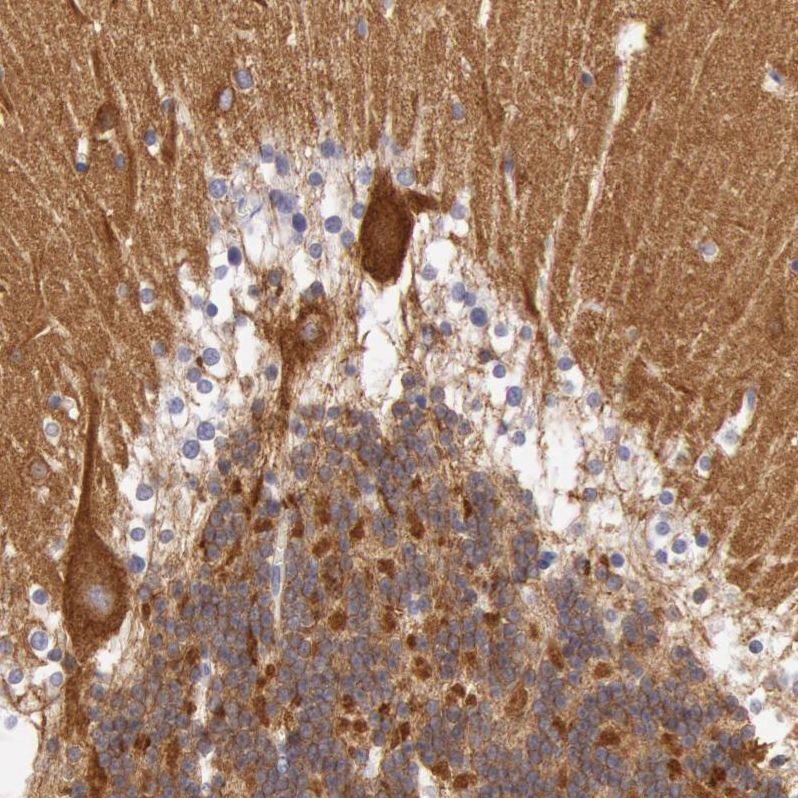

Immunohistochemical staining of human hippocampus shows strong cytoplasmic positivity in pyramidal cells.